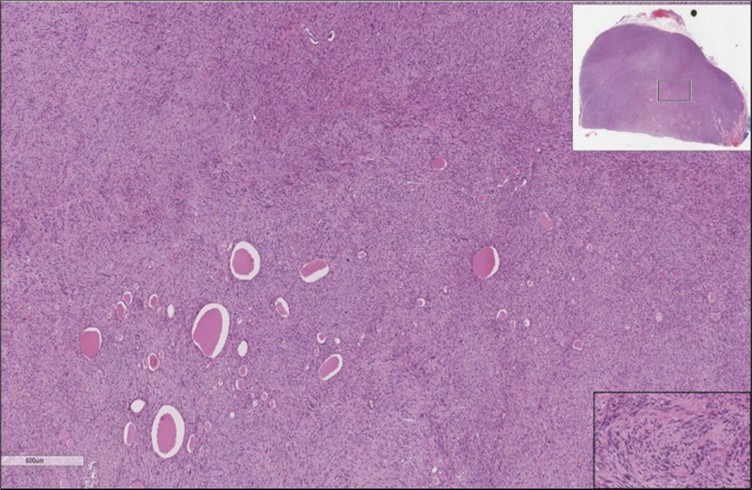

When diagnosing thyroid swelling, imaging studies have been helpful in differentiating malignant from benign tumors with US being used as an initial evaluation tool when assessing thyroid nodules. Tumors are categorized based on composition, echogenicity, shape, margin and echogenic foci into added scores determined by the TI-RADS system, which determines the need for FNA 13. Other imaging modalities include MRI and CT. However; radiological assessment does not distinguish between the types of thyroid cancer, and therefore FNA and biopsy are of crucial importance 3, 6. On a pathologic sample, LMS appears as spindled eosinophilic cells with elongated blunt-ended or cigar-like nuclei arranged in fascicles 2, 7 (Figure 1, Figure 2, Figure 3). Despite the unique microscopic morphology, LMS cannot be distinguished from other spindle cell tumors such as spindle cell variant of medullary thyroid cancer, anaplastic thyroid

Figure 2.Left thyroid On a Higher power, few thyroid follicles are noted and the lesion is composed of spindle cells with sweeping fascicles (H&E, ×200).

cancer, or other metastatic tumors without further testing with genetic or molecular studies 3, 7. Immunohistochemical testing plays a vital role in differentiating LMS from such similar tumors as it stains positive for vimentin and smooth muscle actin (SMA), and is variably positive for HHF35, desmin (50%-100%), and H-caldesmon 3, 6. Moreover, there were no reported cases where thyroid LMS stained positive for thyroglobulin, cytokeratin, calcitonin, chromogranin, or protein S100 3. Our patient’s left thyroid biopsy showed the characteristic microscopic features and was positive for SMA, desmin, caldesmon, P63 with patchy EMA (Figure 1, Figure 2, Figure 3, Figure 4) as well as her liver biopsy (Figure 5, Figure 6, Figure 7); whereas her right thyroid showed clear papillary thyroid cancer cell features (Figure 8, Figure 9).